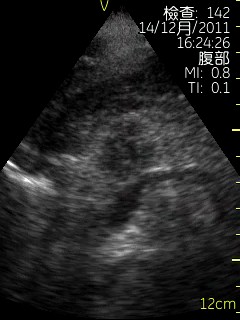

Vscan临床图片 腹部